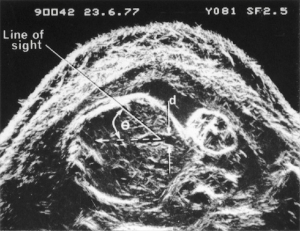

- Scan planes commonly used in babies’ heads

Scans – Paediatric